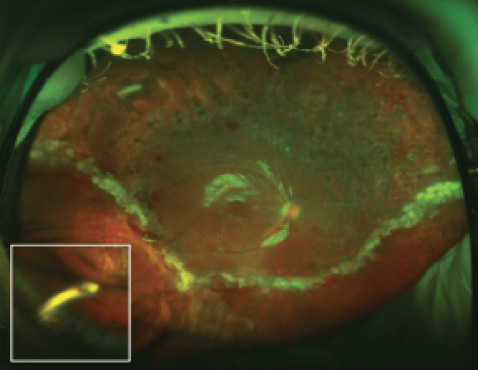

Figure 2. Quiescent PDR 4 weeks after repair of a TRD. A dexamethasone intravitreal implant 0.7 mg was injected preoperatively and left near the vitreous base under silicone oil (inset).

Because this implant inhibits multiple inflammatory cytokines and releases the active drug over a period of 3 to 5 months, it permits flexible planning and keeps inflammation and rebound neovascularization at bay throughout the postoperative period.13 In our experience, the efficacy of the implant is not diminished by the use of silicone oil tamponade after surgery, and we have not seen any complications using it with silicone oil (Figure 2).13